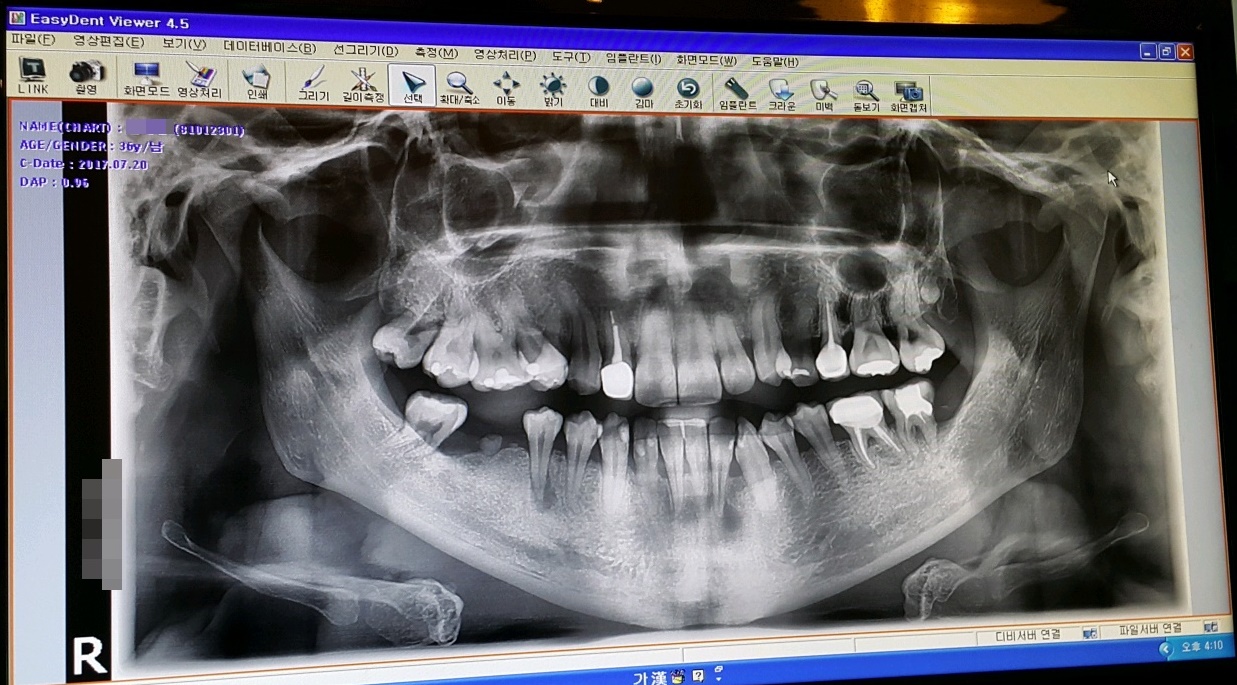

3년전 부정교합 시작하기 전의 내 치아 상태는 지금 생각해 보면 정말 최악?? 이였다..

썩은치아와, 부정교합으로 인해 삐뚤어진 치아들...

교정때문에 발치했던 치아포함 임플란트를 해야할 날이 다가왔다...

해서 임플란트 포함 치료할 치아들 견적 상담 받은 결과...

교정하는 도중 보철 붙혀놓은 치아 사이에 충치가 생기는 바람에

앞니 치아는 미관상 어쩔수 없이 무조건 해야될테고...

좀 오래전? 치료 했었던 윗쪽 어금니와, 그 앞의 치아도 다시 크라운을 해야하고...

오른쪽 아래 어금니는 양쪽으로 받혀주는 치아들도 없는상태에 보철기가 당겨주는 역할까지 하는 바람에

뿌리쪽이 곧 뽑아야 할 만큼 너무 많이 빠져나와서 어쩔수 없이 제거하고 임플란트까지 하기로 했다.